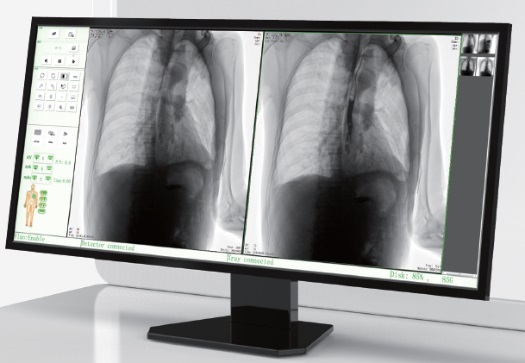

高品質影像鏈 讓您看的更清晰 PLX8500C/D

● 無縫對接醫院PACS系統,幫助實現信息共享、遠程診斷。